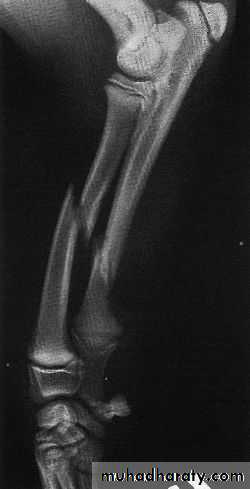

- complete ( subdivided according to the geometry into transverse , oblique , spiral , comminuted , segmental )

COMPLETE FRACTURES